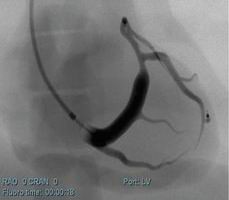

冠狀動脈介入手術(shù)模塊

可練習(xí)冠狀動脈支架手術(shù)的完整過程:造影診斷、導(dǎo)絲通過、導(dǎo)引導(dǎo)管的放置、預(yù)擴張、自擴張支架放置、后擴張、以及再造影等